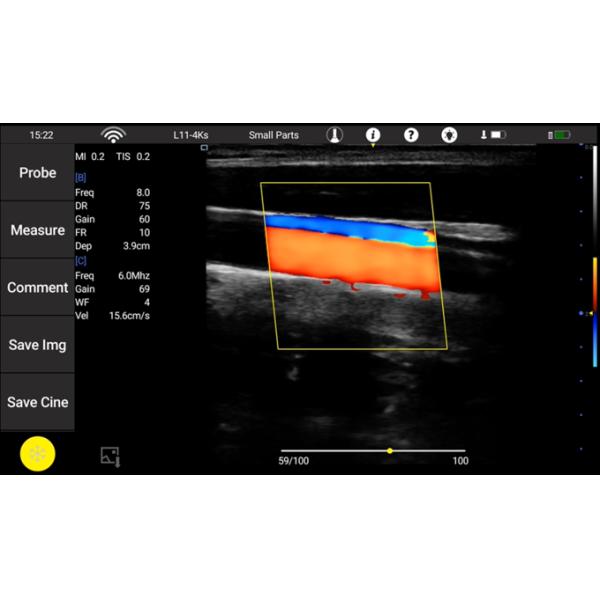

Modes : B, M, 2B, THL, Color, Power, PW (only Color Doppler Version Have Color, Power, PW)

Ultrasound Machine Probes Wireless Ultrasound Probe Cardiac Convex Detachable Transducers

| Design of the innovation | 1. Wireless connection between ultrasound probe and display; Any conventional tablets can transform into an ultrasound machine(Supports lOS, Android and windows) Images can be shared within one click. 2. An ultrasound machine with only 160g light weight, Convenient for hand-carry to anywhere. 3. Patented detachable probe head and main unit; More cost effective and convenient to meet the needs of different clinical applications. Freeze, unplug,plug, 3 steps to detach probe lens for different applications. |

| Modes | B, M, 2B, THL, Color, Power, PW (only color Doppler version have Color, Power, PW) |

| Application package | Abdomen,Small parts, Vascular, Obstetrics,Gynecology,Cardiology, Neurology,Urology, Orthopedics, Anesthesia |